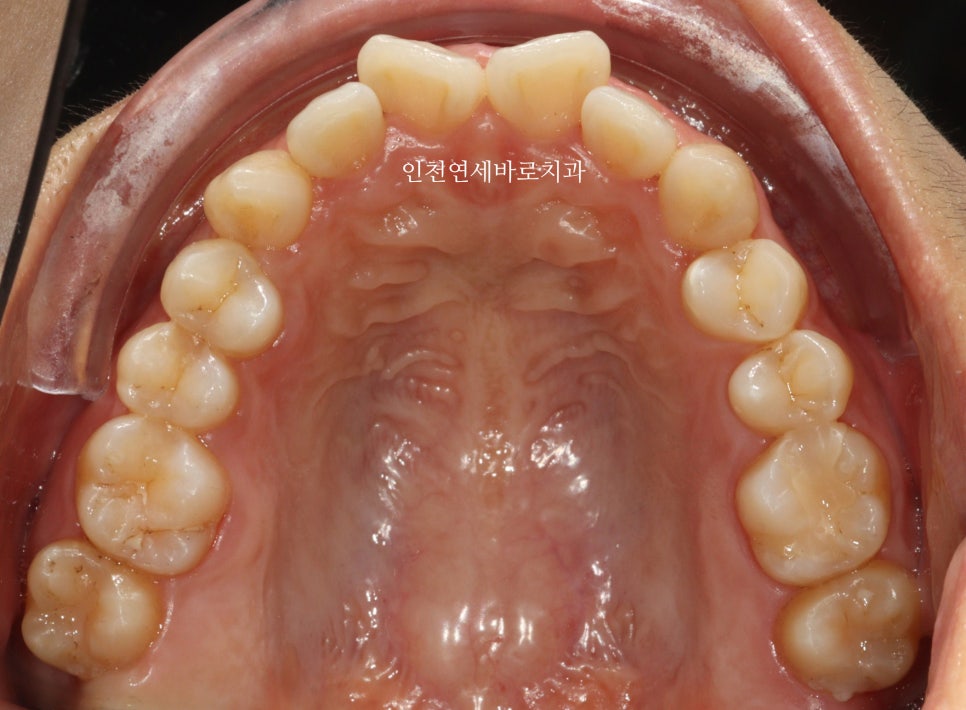

삐뚤삐뚤한 앞니를 고치고 싶어오셨습니다

인비절라인 라이트로 진행하기로 하고 장치 제작을 했습니다.

전후 비교입니다

전 후 교합의 비교입니다.